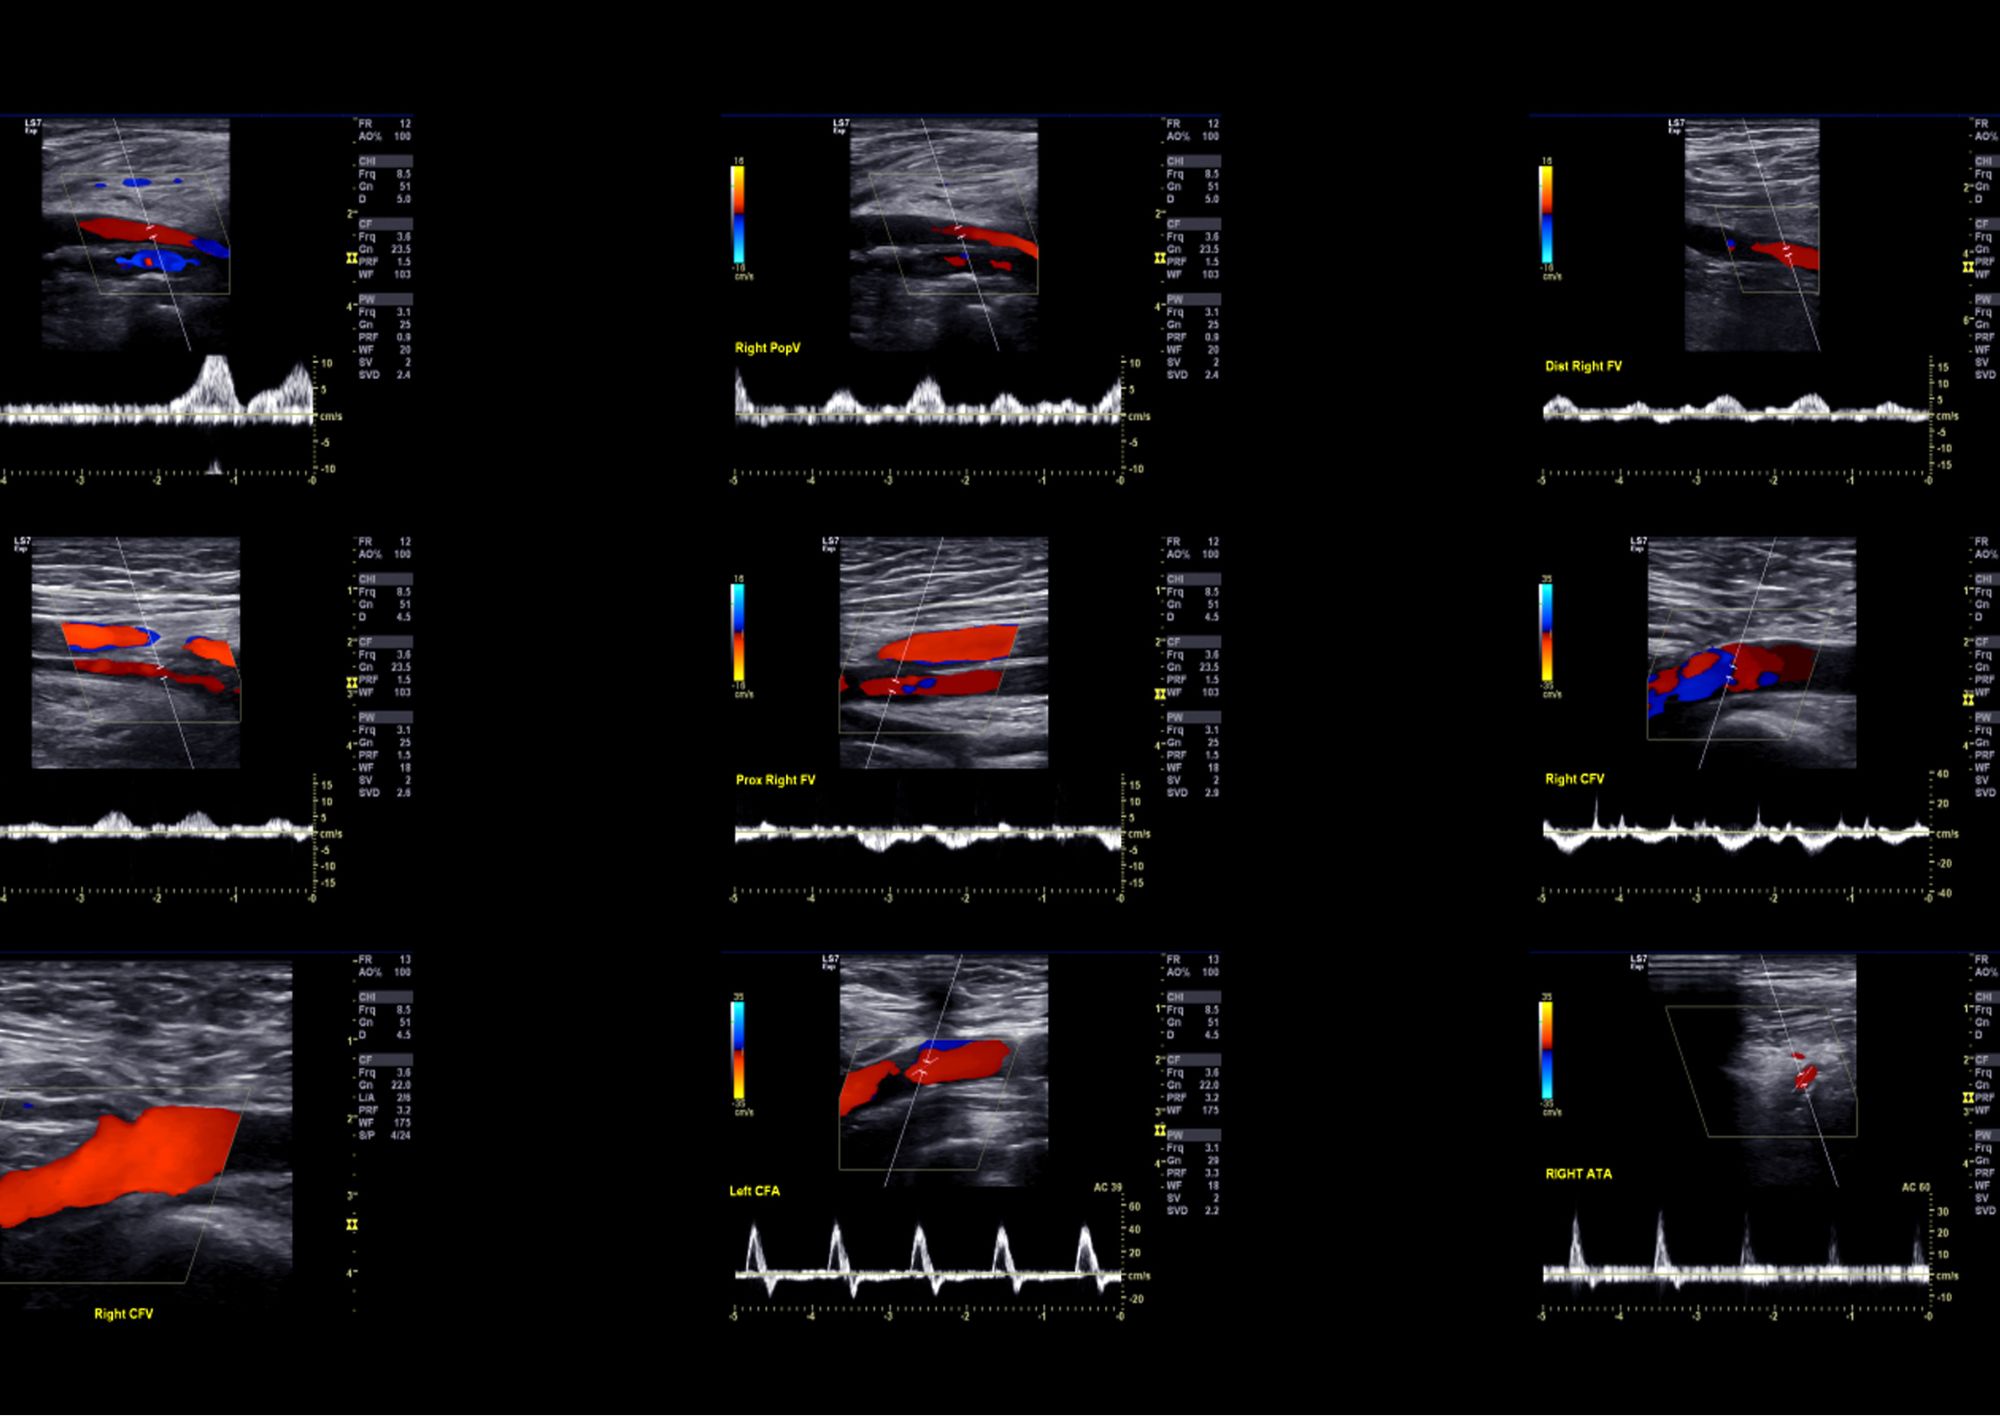

Presso il nostro poliambulatorio puoi effettuare una visita con un angiologo a Roma per valutare sintomi come caviglie gonfie, dolore alle gambe, crampi notturni o comparsa di capillari evidenti. Il medico utilizza tecniche diagnostiche come l’ecocolordoppler venoso e arterioso, fondamentali per analizzare il flusso sanguigno e identificare eventuali restringimenti, ostruzioni o reflussi.

Spesso, per completare la visita, è necessario eseguire un ecocolordoppler delle gambe o dei vasi del collo. Questi esami non invasivi consentono di studiare la morfologia dei vasi sanguigni e di valutare la velocità e la direzione del flusso ematico. I risultati aiutano a identificare restringimenti, ostruzioni o reflussi venosi.